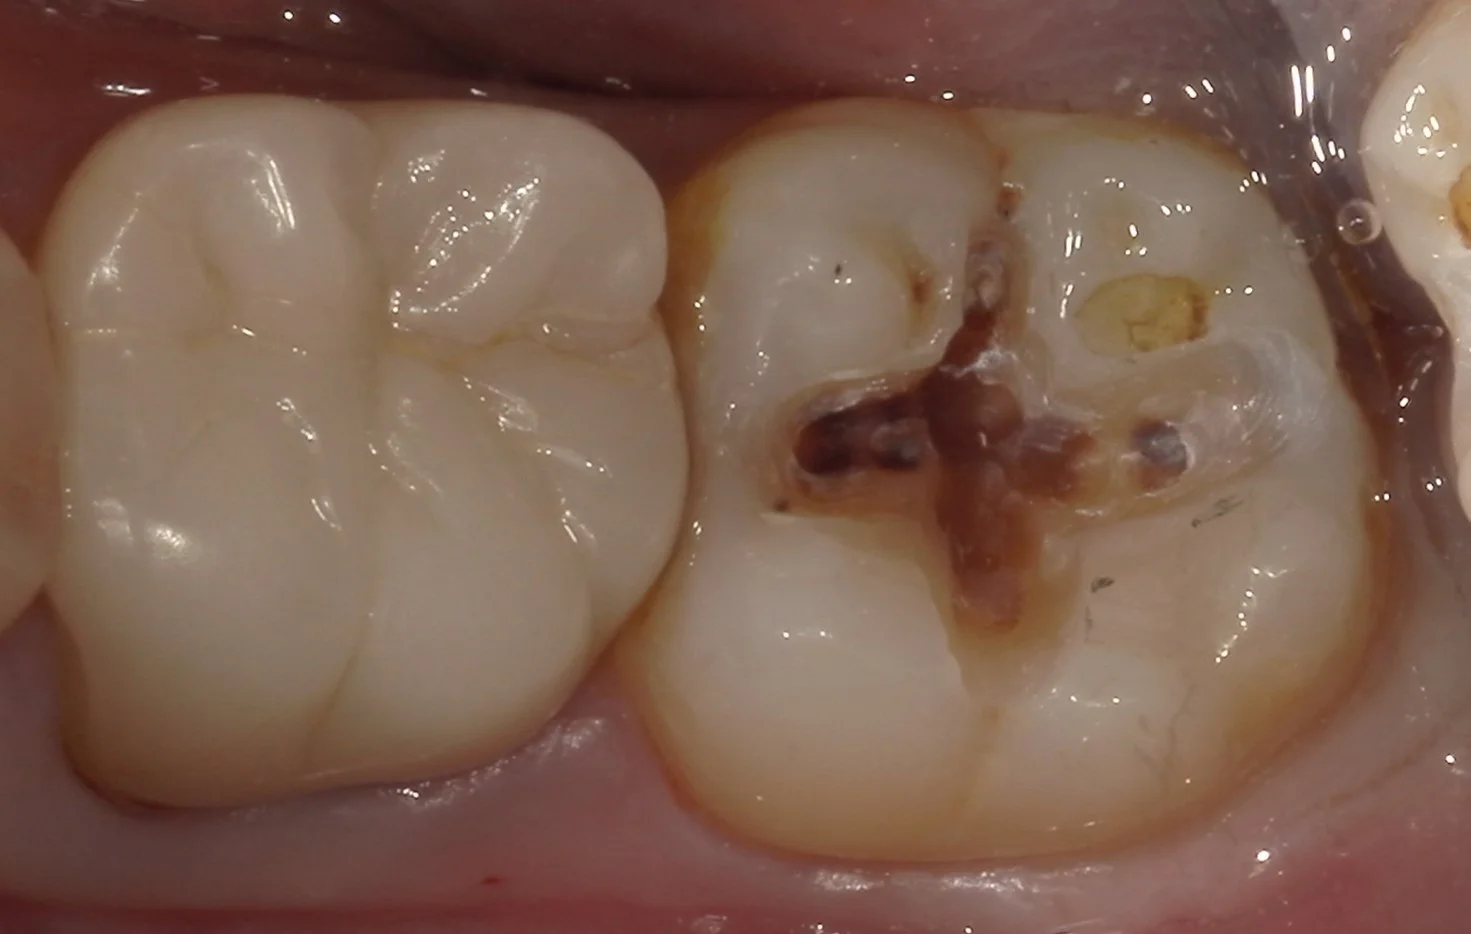

では、実際に詰め物のみを外し、虫歯を見えやすくしたものを見てみましょう。

ご覧の通りです。

前の詰め物を取りきらずに、その部分だけを治療することを補修修復と言いますが、これは何でもかんでもに使える手法ではありません。

特に今回のように内面に虫歯が入り込んでるのが見た目でも分かるようなレベルの場合は、一度詰め物と虫歯を完全に取りきった方が治療の予後は圧倒的に良くなります。